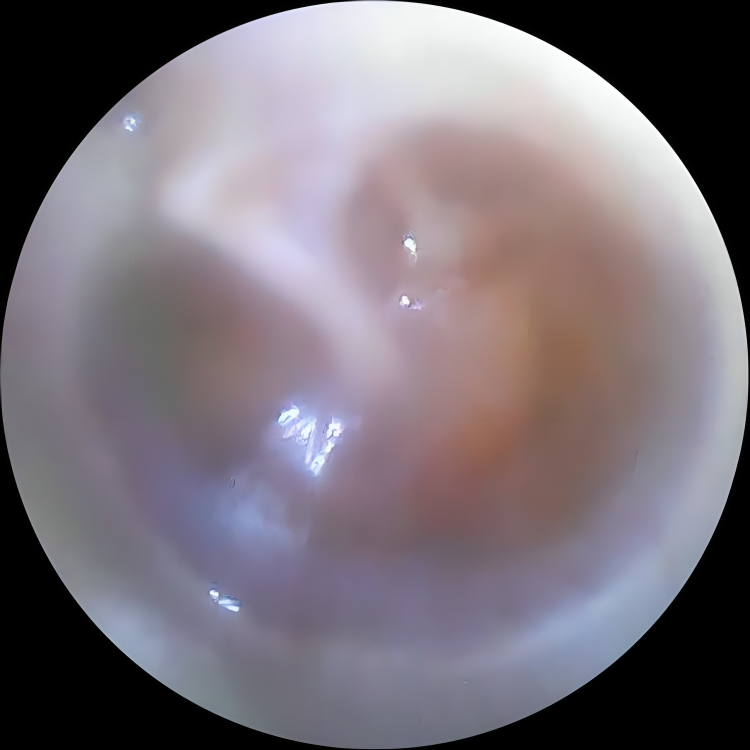

Read MoreAdvanced camera-based examination for accurate diagnosis of ENT concerns.

He is skilled in endoscopic evaluations, minimally invasive ENT procedures, vertigo assessment and advanced ear - nose - throat care, ensuring precise and patient-friendly treatment.